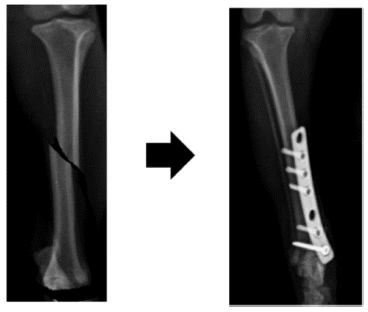

골절합용 판은 외부 충격에 의하여 부러진 뼈를 고정시키고 뼈를 원래 형태로 회복시키기 위한 골절 수술에 사용된다. 골절 합용 판으로 부러진 뼈를 감싼 뒤 판의 구멍에 맞추어 뼈에 구멍을 형성시킨다. 형성된 구멍에 나사를 삽입하여 부러진 뼈들을 원래 형태로 고정시켜 서로 붙게 한다[1].

Fig. 1에 골절합용 판을 이용하여 부러진 뼈를 치료하는 과정을 도시하였다. 골절합용 판은 부러진 뼈 주변을 감싸기 위하여 폭과 너비가 커야 하고, 수술 후 이물감을 최소화하기 위하여 두께가 얇아야 한다.

Fig. 1

Fracture treatment using bone plates and screws

KSPE_2022_v39n4_291_f001.jpg